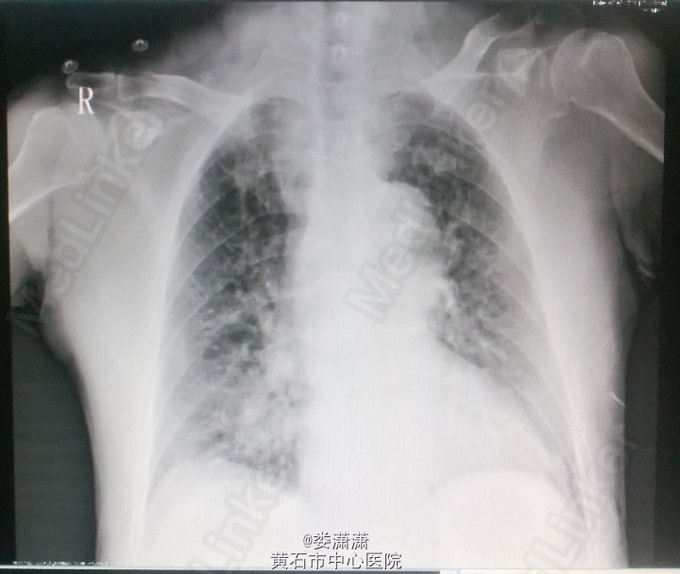

查体——体温 36.2℃,脉搏52次/分,呼吸21次/分,血压90/42mmHg。精神状态差,表情痛苦,面色苍白,四肢湿冷,口唇发绀。双肺呼吸音清,两肺未闻及干、湿罗音。心音减弱,心律齐,各瓣膜听诊区未闻及杂音。余查体无明显异常。 辅查——血常规:白细胞计数14.49G/L;肌酐 179umol/l;随机血糖 17.0mmol/l;入科时TnT 0.092ug/l,急诊介入手术后复查心肌酶:CK 7760 IU/L,CK-MB 455 IU/L,TnT 98.8ug/l;尿酸584umol/l;心脏彩超见图1;胸片见图2-3。